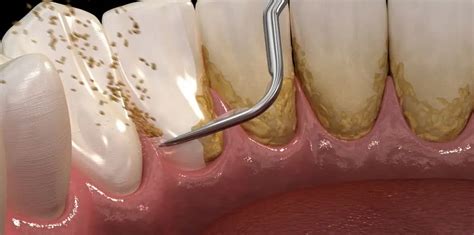

- Curetaje: Las curetas dentales son dispositivos manuales con formas muy variadas, de tal manera que consiguen adaptarse perfectamente a la superficie de los dientes. Permiten llegar bien a los espacios que hay en el surco de la encía. Allí se acumula el denominado sarro subgingival, especialmente nocivo para los tejidos gingivales al estar colonizado frecuentemente por patógenos periodontales muy dañinos.

En Clínica Dental Letamendia, empleamos tecnología de ultrasonidos de última generación para quitar el sarro de los dientes de manera precisa y confortable. El proceso incluye también el uso de instrumental manual especializado (curetas) para el refinado de superficies radiculares y la eliminación de sarro en áreas de difícil acceso.

Cuando el sarro duro ha progresado causando gingivitis o enfermedad periodontal, en Clínica Dental Letamendia implementamos protocolos de tratamiento integral que pueden incluir curetajes radiculares, terapia antimicrobiana y seguimiento periodontal especializado.